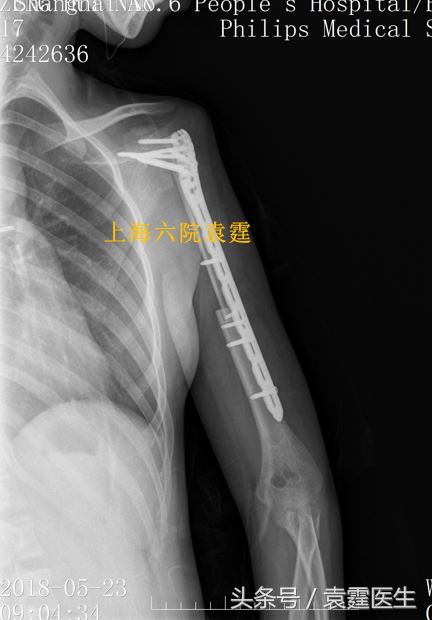

相对普通关节置换,用腓骨融合肩关节是目前功能较好的治疗恶性肱骨近端的方法。术后的患者可以用患肢做重体力活,可以满足日常的生活需要。

恶性肿瘤切除游离腓骨血管吻合肩关节融合术